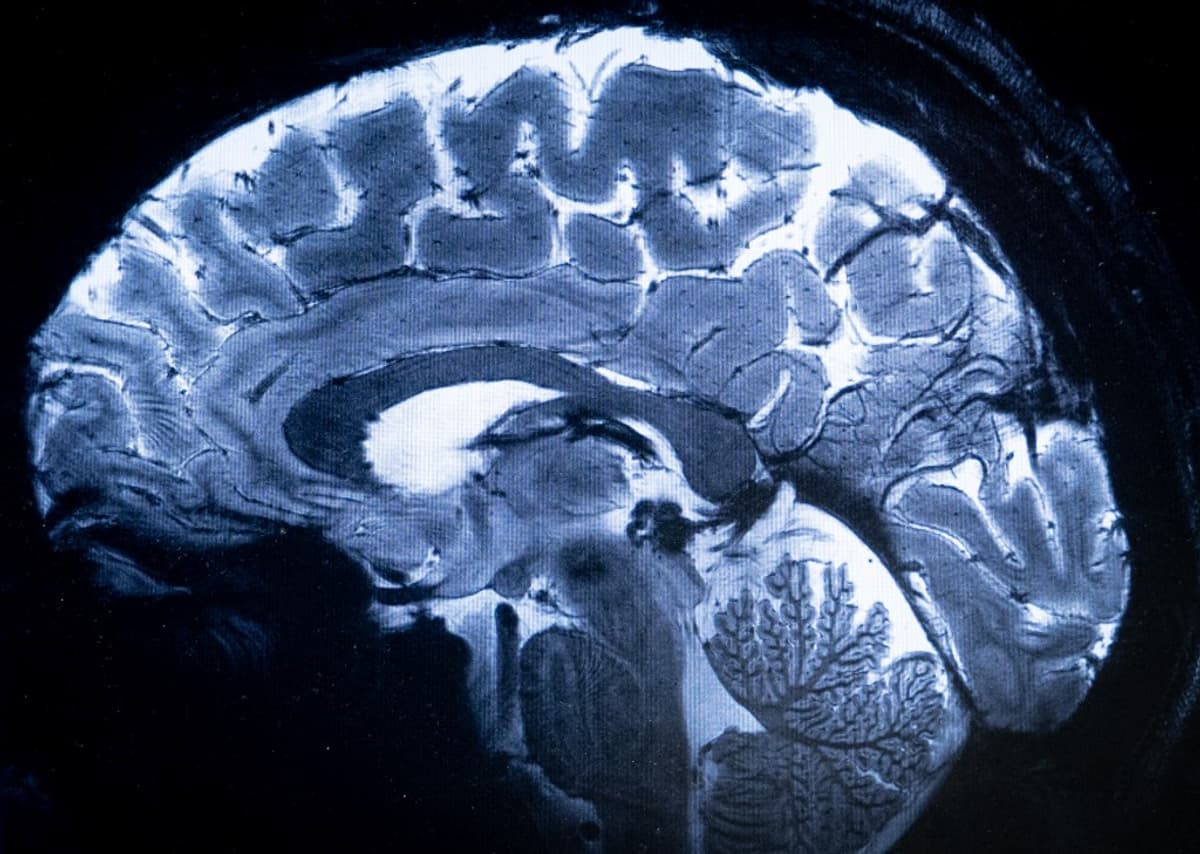

"On a un niveau de finesse jamais atteint au CEA", se félicite Alexandre Vignaud, physicien, directeur de recherche au CEA. Le champ magnétique de cet aimant hors norme atteint 11,7 T (tesla), permettant l'obtention d'images 10 fois plus précises que celles produites actuellement dans les hôpitaux, où la puissance des IRM ne dépasse pas 3 tesla.

Le tout en seulement quatre minutes, avec un résultat pour lequel un IRM d'hôpital prendrait "théoriquement plusieurs heures", "irréaliste pour le confort du patient et parce que ses mouvements 'brouilleraient' l’image", comme l'explique le CEA dans un communiqué.

"Avec cette machine, on peut voir les tout petits vaisseaux qui alimentent le cortex cérébral ou des détails du cervelet qui étaient quasi invisibles jusqu'alors", souligne Alexandre Vignaud.